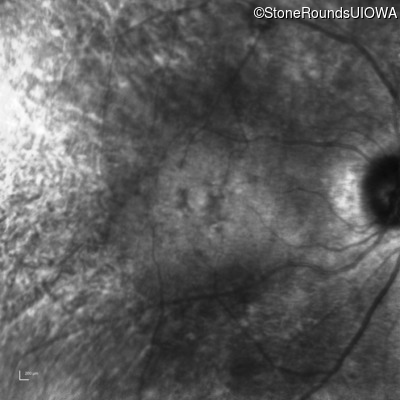

Infrared Fundus Photograph - Right - 20/25

Exemplar

Infrared Fundus Photograph - Left - 20/70 +1